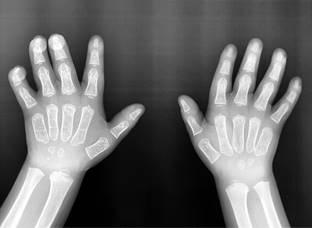

En ultrasonido (US) abdominal se detectó esplenomegalia: bazo de 85 mm con ecogenicidad y forma conservada. Hígado con tamaño en el límite superior máximo normal. Radiografía de manos con dorsiflexión de articulaciones interfalángicas proximales y distales (Figura 3). Ecocardiograma: situs solitus en levocardia, sin patología valvular. Umbral auditivo disminuido (60 dB (VN 0-25 dB)). Evaluación psicológica: trastorno del desarrollo psicomotor, trastorno por déficit de atención clínico y disfasia del desarrollo.

Figura 3: Radiografía anteroposterior de manos que muestra dorsiflexión de articulaciones interfalángicas proximales y distales.